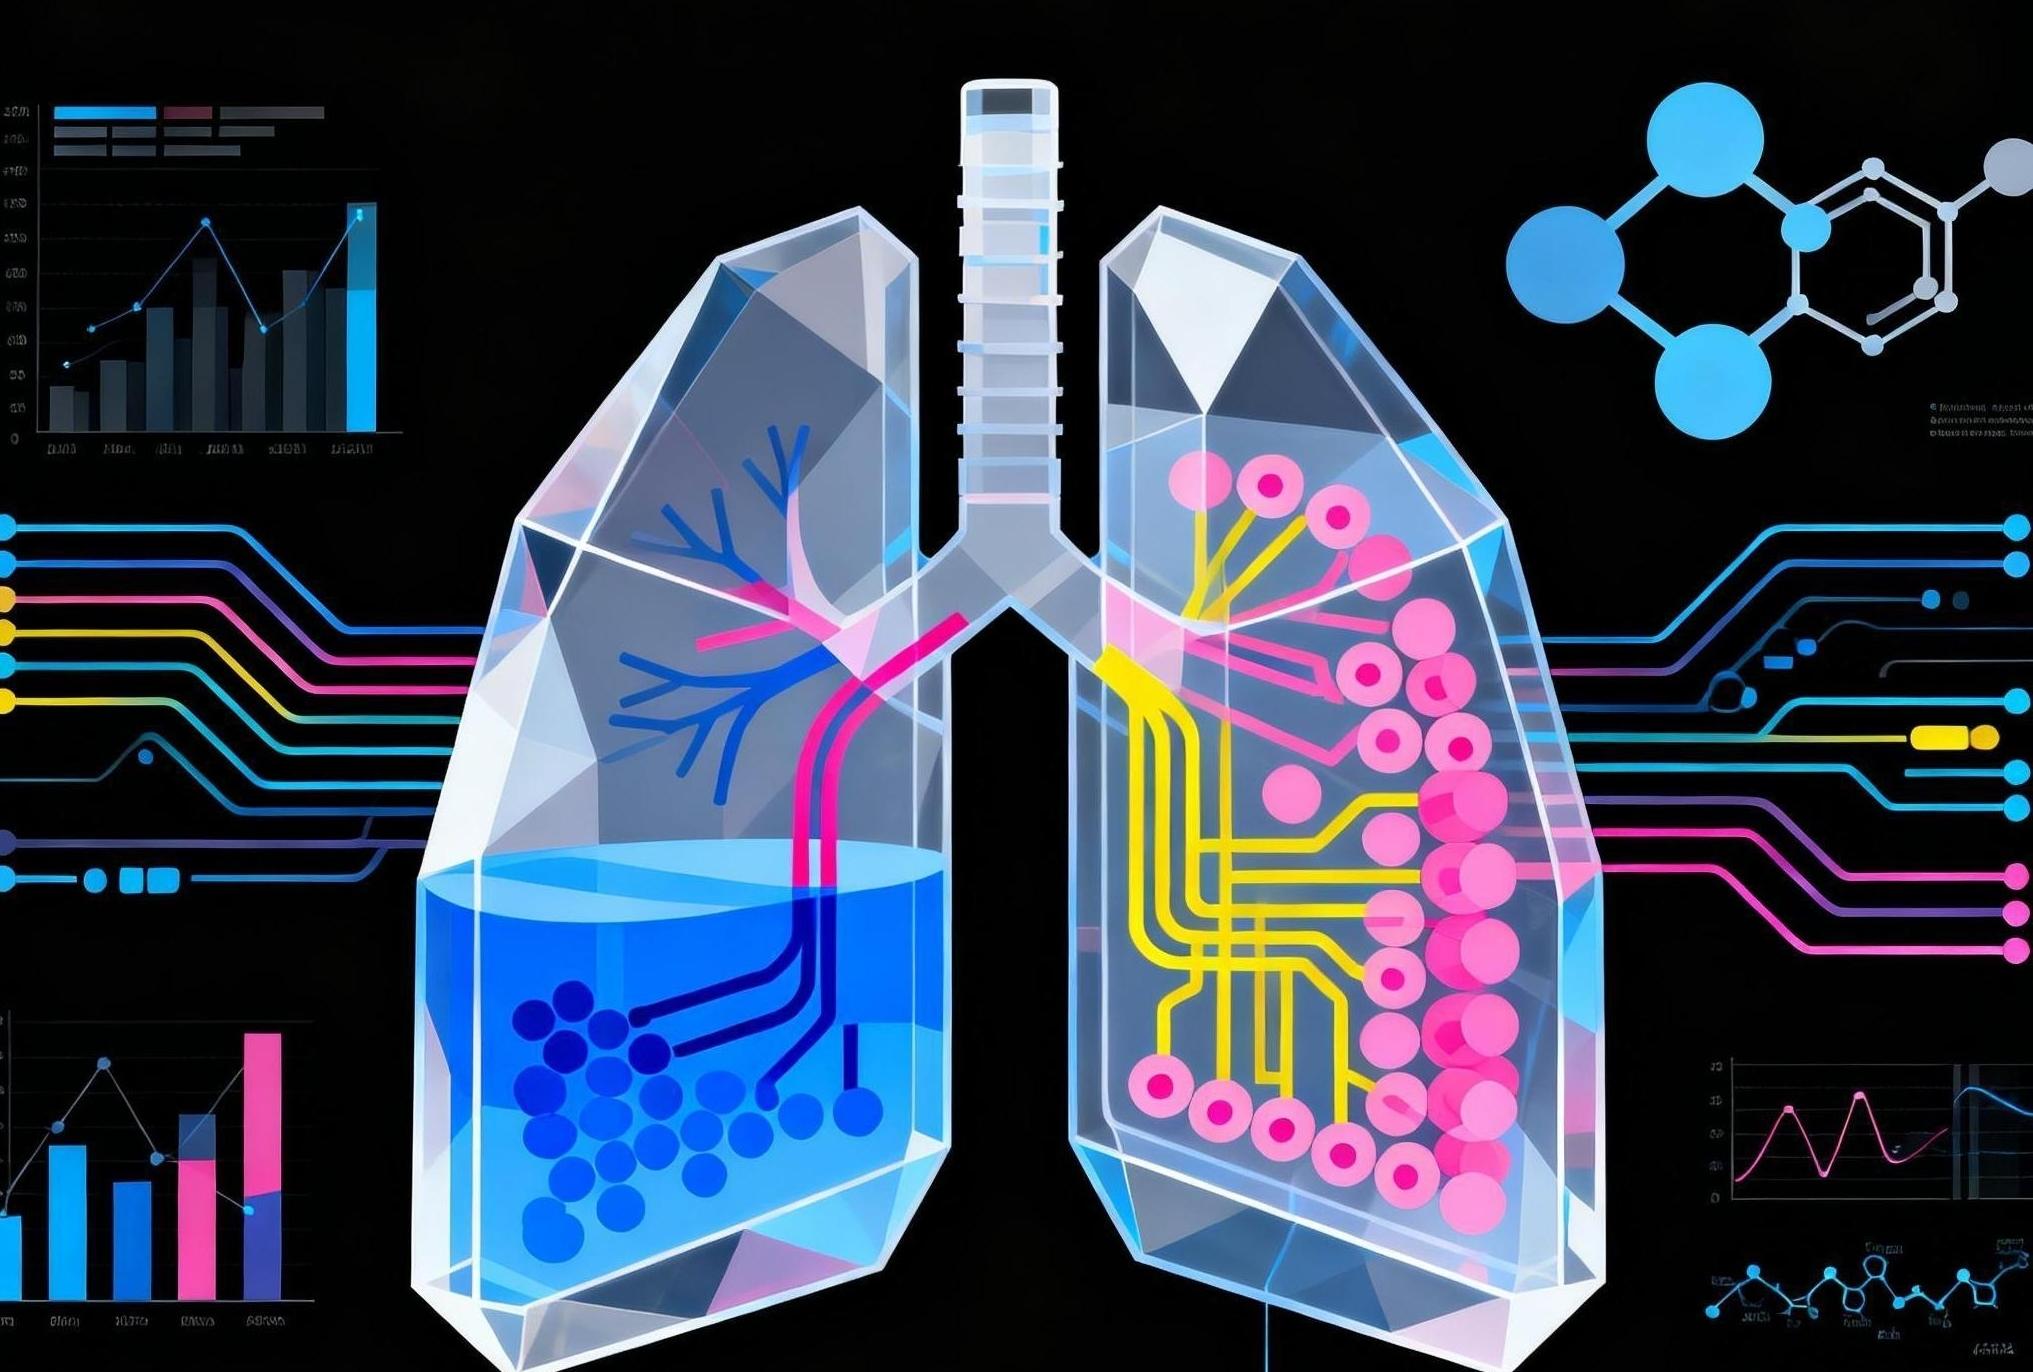

首個基因一致的人源“肺芯片”問世